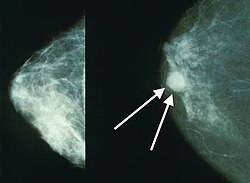

Ինչու է վաղ հայտնաբերումը կարևոր

Մասնագետները ընդգծում են, որ կրծքագեղձի քաղկեղը վաղ փուլերում հայտնաբերելու դեպքում բուժման արդյունավետությունը զգալիորեն բարձր է։ Ինքնազննման սովորույթը, պարբերական բժշկական հետազոտությունները և բժշկի ժամանակին դիմելը կարող են փրկել կյանքեր։